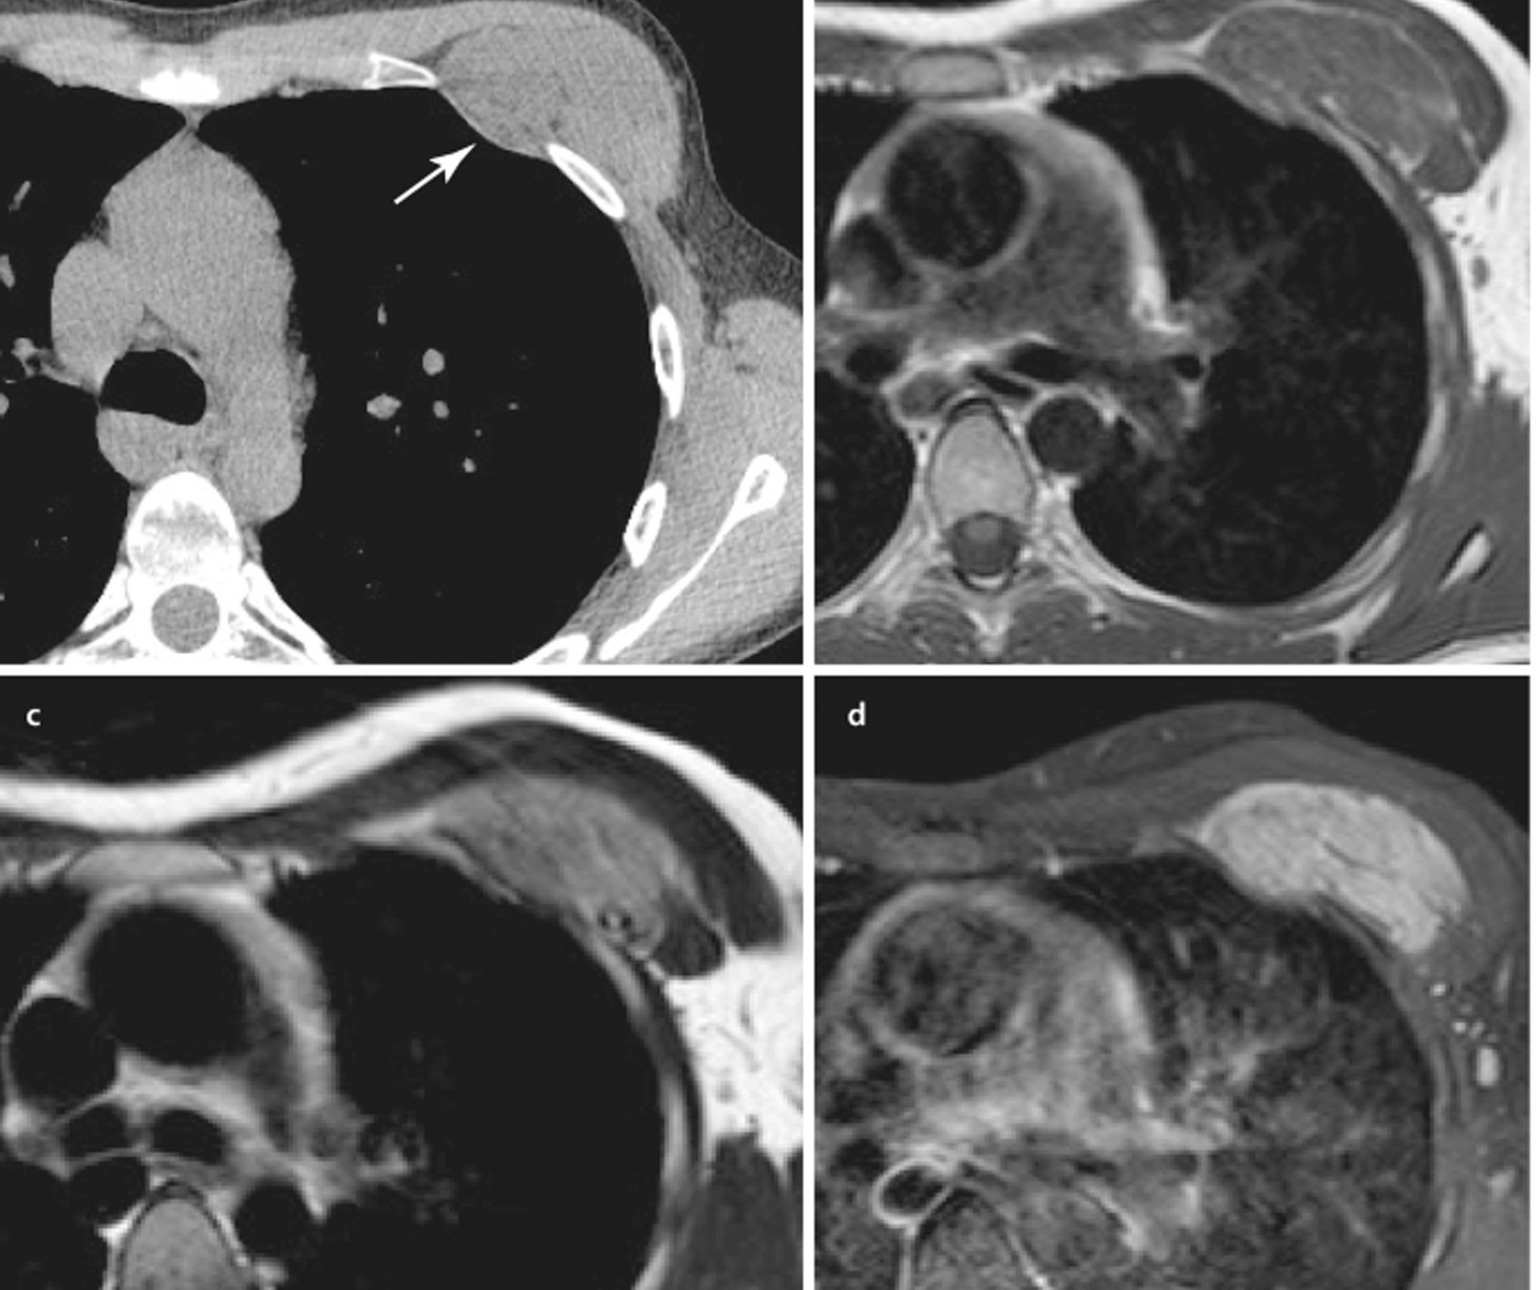

The diagnosis of chest wall tumors typically involves a combination of imaging studies, such as X-rays, CT scans, or MRI scans, to visualise the tumour and assess its extent. A biopsy, which involves taking a small sample of the tumour for examination under a microscope, is often performed to determine whether the tumour is benign or malignant.